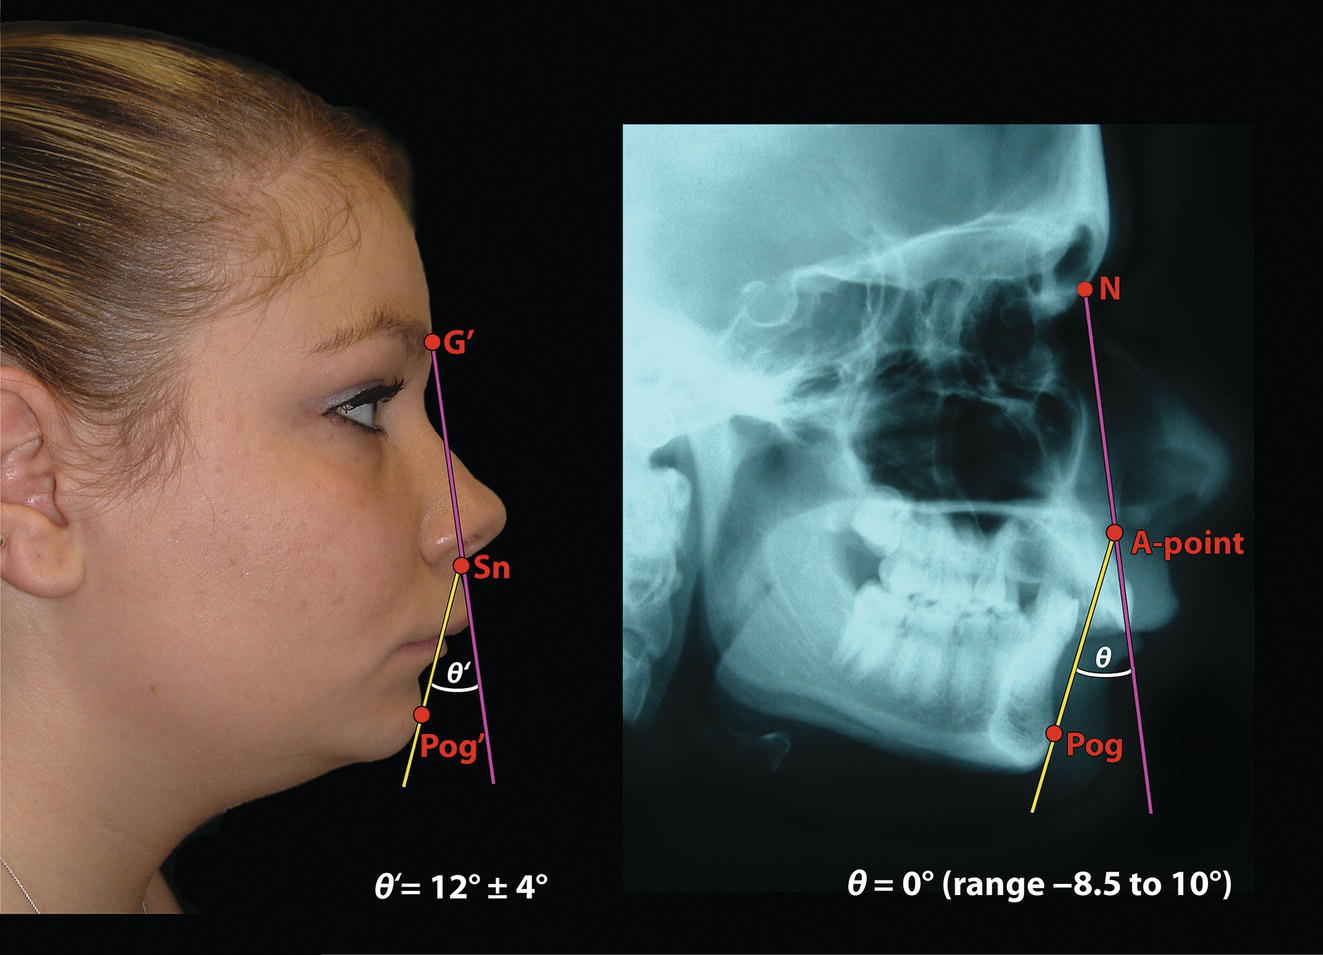

‘It is the common wonder of all men, how among so many millions of faces, there should be none alike’. Sir Thomas Browne (1605–82), English physician and writer, Religio Medici (1643)1 Individual variability is a fundamental principle in human biology. One of the most variable and distinguishable parts of the human body is the craniofacial complex. Clinicians will often compare a patient’s craniofacial measurements and proportions to the so‐called population norms (normative values) or even to classical ideals. However, Simon (1926) stated: ‘all we ever find are variations; an exact, ideal normal does not exist, cannot exist. And this is our enigma; in theory we will never find the normal, in practice we forever feel its need and apply it constantly’.2 The use of population norms may be logically enhanced by evaluating normal ranges of variability. Therefore, clinicians must have a thorough understanding of the normal ranges of variability in every aspect of craniofacial form, depending on age, sex and ethnic variability. Developmental disorders, as well as traumatic injuries and pathological conditions, may lead to deformities of the head and the face. Therefore, clinicians need to have a thorough understanding of the normal anatomy and morphological range of variation of the craniofacial complex in both males and females of different ages and ethnic groups, to act as guidelines when treatment planning the restoration of normal craniofacial proportions. Classifications that are useful for descriptive purposes include: A proportion index provides a numerical expression of the proportionality of a region of the craniofacial complex. The use of proportion indices dates back through the history of craniometry, particularly in the late nineteenth century. Linear (chord) or surface (arc) distances of the skull were measured between a variety of defined craniofacial landmarks; with any two measurements, the smaller was expressed as a percentage of the larger in order to provide a proportion index value. These could be used to provide an indication of skull shape. Figure 8.1 Determination of the normality or abnormality of any craniofacial measurement (or proportion index value) obtained from patients may be evaluated by comparison with the normative values obtained from a normal (average representative) population sample. The normal range of measurements is provided by the mean ±2 standard deviations (SD). The shape of the normal distribution curve shown is determined by the population standard deviation. Craniofacial parameters with small SDs have narrow, taller curves and those with large SDs have broader, flatter curves. Approximately 68% of all values fall within the range of ±1 SD from the mean and 95% within the range of ±2 SD from the mean. The normal range of variability for any craniofacial parameter is taken as being equal to the mean ±2 SDs. Greater differences may be perceived as deformities of gradually increasing severity. The leading researcher in the field of craniofacial anthropometry from the mid‐1960s to the early 2000s was Leslie Farkas, from the University of Toronto. Farkas et al. collected a large quantity of highly relevant anthropometric data between 1968 and 1984, from 2564 individuals.3 These data were used to provide 166 individual facial ratios, presented as proportion indices. In the creation of an index, the smaller measurement is multiplied by 100 (numerator) and divided by the larger measurement (denominator). Thus, a proportion index involves two linear craniofacial anthropometric measurements, with the smaller being expressed as a percentage of the larger. Proportion indices permit objective, quantitative assessment of facial morphology and proportions. Farkas3 identified two basic categories of proportion indices: Each proportion index will have a mean index value and a range of variation for a given population group, based on age, sex and ethnicity. The standard deviation (SD) determines the normal (average) range of variability of an index, from 2 SD below to 2 SD above the mean. Index values within this normal range are regarded as variations of normal proportions.4 Measurements within ±1 SD of the mean are regarded as optimal. The relationship between two measurements is disproportionate if the proportion index value is outside the normal range (Figure 8.1).4 For a number of facial parameters, single morphological measurements or proportion index values may have a large SD and, therefore, wide normal ranges of variation; as such, only measurements or proportion index values which differ considerably from the mean of the population will be perceived as deformities. Conversely, other facial parameters may have very small normal ranges of variability, in which case even a small difference from the mean may be perceived as a deformity. The cephalic index (index cephalicus) is a numerical expression of the ratio between the head width (biparietal diameter) and head length (fronto‐occipital diameter) of a living person. The cephalic index (CI) is calculated by the formula (Figure 8.2): Figure 8.2 Cephalic index. Where: The cephalic index is used in anthropometry to classify head types as (Table 8.1; Figure 8.3): Table 8.1 Classification of anatomical head types Index values according to Martin and Saller.5 Figure 8.3 Head types. The highest cephalic index values occur in the Chinese and the lowest values in African Americans. The larger index values of the Chinese differ significantly from those of whites or blacks (Table 8.2).6 A comparison of the cephalic index values of three ethnic groups was undertaken; North American Caucasians, northern European (German) and eastern European (Czech). The index values indicated a mesocephalic head type for both sexes of North American Caucasians and northern Europeans; and a brachycephalic (short‐wide) head type for the eastern Europeans.6 The head circumference is measured in the horizontal plane around the head, through the glabella and opisthocranion. However, it may be measured across ophyron (the point ‘On’, in the mid‐sagittal plane, of a line tangent to the upper limits of the eyebrows) rather than glabella in order to eliminate the effect of development of the frontal sinuses and superior orbital rims on head circumference.5,7 African Americans have the largest and the Chinese have the smallest head circumference for both sexes. The head circumference is slightly larger for blacks than for whites for both sexes.6 The initial step in facial analysis involves the examination of the face in frontal view in order to assess the overall facial shape. The variety of facial shapes is almost limitless. However, a simple assessment will allow an overall categorization of the basic facial shape. The basic facial shape in frontal view may be any combination of the following: Table 8.2 Cephalic index of three ethnic groups Data modified from Farkas.6 SD = standard deviation. Table 8.3 Head circumference of three ethnic groups Data modified from Farkas.6 SD, standard deviation. Figure 8.4 Facial height‐to‐width ratios. Variations in facial height and width result in an innumerable variety of the three basic facial shapes (round, square and triangular). For example, an oval facial type is a combination of an overall round face combined with increased vertical facial height and/or reduced facial width. The relationship of vertical facial height to facial width is an important indicator of overall facial shape. There are three methods of evaluating the vertical facial height‐to‐width proportion. These may be presented as proportions, percentages or indices: The facial index (index facialis or index of the morphological face height) is a numerical expression of the ratio between the facial height (nasion to menton) and the bizygomatic facial width (zygion to zygion) of a living person. The facial index (FI) is calculated by the formula: Where: The facial index is used in anthropometry to classify faces as (Table 8.4; Figure 8.6): Figure 8.5 Facial types according to Albrecht Dürer. (Modified from Dürer, 15288.) Figure 8.6 Facial types. Table 8.4 Classification of anatomical face types Index values: male according to Garson, 1885;9 and female according to Martin and Saller, 1957.5 The term facial divergence was introduced by the orthodontist‐anthropologist Milo Hellman,10 although the concept had been described by Albrecht Dürer (1528) (Figure 8.7).8 It is essentially a description of the slope or inclination of the face in the sagittal plane (Figure 8.8). It is determined by the sagittal position of soft tissue pogonion (Pog’) and subnasale (Sn) relative to a vertical line dropped from glabella (G’), with the subject’s head in natural head position. The factor that discriminates and distinguishes facial divergence from profile convexity or concavity is the sagittal position of subnasale (Sn) relative to the G’‐Pog’ line. In order for the face to diverge anteriorly or posteriorly, yet not to exhibit signs of convexity or concavity, subnasale (Sn) must be on or nearly on the G’‐Pog’ line; i.e. the upper facial plane (UFP, G′‐Sn) and the lower facial plane (LFP, Sn‐Pog’) are in a straight line, but diverge anteriorly or posteriorly. Figure 8.7 Facial divergence according to Albrecht Dürer. (Modified from Dürer, 15288.) Figure 8.8 Facial divergence. Anthropometric data from North American Caucasian males and females with untreated Class I dental occlusions describing normal facial divergence and ranges of variability has been provided.11 Mean values of facial divergence are negative, with the faces being slightly posteriorly divergent. Anterior divergence does not occur until two standard deviations from the mean. Facial divergence is essentially an ethnic variation in facial profile form. With a straight profile, i.e. no excessive profile convexity or concavity, anterior or posterior facial divergence is compatible with a normal maxillo‐mandibular and dental occlusal relationship. Figure 8.9 Facial profile contour according to Albrecht Dürer. (Modified from Dürer, 15288.) Figure 8.10 Facial profile contours. The contour of the facial profile may be described as convex, straight or concave. This concept was described by Albrecht Dürer (1528) (Figure 8.9).8 With the patient in NHP, the overall contour of the facial profile may be described by the relationship between two lines: the upper facial plane (UFP), connecting glabella (G’) to subnasale (Sn), and the lower facial plane (LFP), connecting subnasale to soft tissue pogonion (Pog’). In a straight profile, these two lines form a nearly straight line. Such a facial profile is termed orthognathic (Greek orthos: correct or straight; gnathos: jaw). An angle between these two lines indicates facial profile convexity (pogonion behind relative to subnasale in the sagittal plane), or facial profile concavity (pogonion ahead relative to subnasale in the sagittal plane). A convex profile indicates a skeletal Class II jaw relationship (and/or sagittal chin deficiency), and a concave profile indicates a skeletal Class III jaw relationship (and/or sagittal chin excess). However, profile convexity or concavity does not of itself indicate whether the maxilla or mandible/chin is at fault (Figure 8.10). Legan and Burstone12 described the angle of facial convexity for the soft tissue profile. It is formed by the two intersecting lines, the UFP (G′‐Sn) and the LFP (Sn‐Pog′). The mean value is estimated to be 12° ± 4°. An increase in the angle in a clockwise direction is positive; anticlockwise is negative. A high positive value suggests facial profile convexity and a Class II skeletal jaw relationship; a smaller positive value, or a negative value, suggests facial profile concavity and a Class III skeletal jaw relationship. However, the value of this angle does not reveal whether the maxilla or mandible/chin is responsible for the sagittal jaw discrepancy. Figure 8.11 Angle of facial profile convexity (facial contour angle). Downs13 described the angle of convexity, formed by the intersection of line nasion to point A (NA) and line point A to pogonion (A‐Pog). Superior extension of the A‐Pog line forms an angle with the NA line; if behind the NA line, the angle is read as positive, indicating a Class II (convex) skeletal profile. A negative angle of convexity indicates a Class III (concave) skeletal profile. Downs provided a range of values from −8.5° to 10°, with a mean of 0°. Again, as with the facial contour angle, the angle of convexity does not determine the localization of the deformity to the maxilla or mandible/chin. An investigation was carried out with the objective of assessing how lower facial profile convexity influences perceived attractiveness. The lower facial profile of an idealized image was altered incrementally between 14° and −16°, creating a range of images which were evaluated by pretreatment orthognathic surgery patients, laypeople and clinicians. A straight profile was perceived as most attractive and greater degrees of convexity or concavity deemed progressively less attractive, but a range of 10° to −12° was deemed acceptable; beyond these values surgical correction was desired. Patients were most critical, and clinicians were more critical than laypeople.14 The facial angle indicates the relative sagittal prominence of soft tissue pogonion. It is formed by the intersection of the true horizontal plane (or Frankfort Horizontal plane) with a facial vertical plane (N′‐Pog’). The angle should be approximately 90°–92°. A greater angle indicates prominence of soft tissue pogonion; an angle less than 90° indicates retrusion of soft tissue pogonion. The soft tissue facial angle does not of itself determine the aetiology of the sagittal position of soft tissue pogonion, which may be due to one or a combination of: Consequently, the facial angle must be used in conjunction with other measurements and analyses. In addition, when constructing the facial vertical line (N’‐Pog’), if the sagittal position of nasion is not acceptable, it may be adjusted to a more ideal position. The alternative is to use soft tissue glabella (G’) rather than nasion. Downs13 described the facial angle as the inferior inside angle in which the facial line (N‐Pog) intersects the Frankfort Horizontal plane. Downs found a mean value of 88° with a range of 82°–95°. It indicates the relative sagittal position of the mandible/chin to the upper face. Figure 8.12 Facial angle. FH, Frankfort Horizontal plane; TrH, true horizontal plane. Figure 8.13 The relationship of the cranial base angle (saddle angle) and anterior cranial base length on the jaw relationship. The relationship of the anterior to the posterior cranial base is of particular importance in the diagnosis of facial profile contour. This relationship depends on the extent of growth at the sphenoethmoidal and spheno‐occipital synchondroses. The cranial base angle (or saddle angle) represents the orientation of the anterior cranial base (SN line) relative to the posterior cranial base (S‐Ba line).15 The average adult values (bearing in mind that there is negligible change in this angle after the age of six years) for the angle N‐S‐Ba are16: As such, the cranial base angle is an important determinant of craniofacial form, as it influences the sagittal position of the face relative to the neurocranium and the sagittal prominence of the mandible relative to the maxilla. A significantly increased cranial base angle contributes to a skeletal Class II jaw relationship, whereas a reduced cranial base angle contributes to a skeletal Class III jaw relationship. If basion is difficult to identify on a lateral cephalometric radiograph, articulare may be used instead, i.e. the posterior cranial base is drawn between sella and articulare. The average adult values for the angle N‐S‐Ar are16: The anterior cranial base length, measured from sella to nasion, may also influence the jaw relationship. For example, increased anterior cranial base length may lead to a Class II jaw relationship, with the maxilla ahead of the mandible in the sagittal plane, whereas reduced cranial base length may lead to a Class III jaw relationship, with the maxilla behind the mandible in the sagittal plane. The average adult values for the anterior cranial base length are16: Figure 8.14 Parasagittal profile contour. An additional and extremely important consideration is the description of the parasagittal profile (Figure 8.14). It is necessary to evaluate the sagittal relationships of the soft tissues from the infraorbital area to the paranasal area to the parasymphyseal area. For example, maxillary hypoplasia may lead to lack of bony support and flattening in the infraorbital region and paranasal hollowing; with a normal parasymphyseal area, this will lead to the appearance of a concave parasagittal profile. The directional pattern of facial growth has a significant effect on facial profile form. Deviations from the normal pattern of jaw growth may be in a predominantly vertical or horizontal direction. Alternative terms are hyperdivergent facial growth pattern (referring to the excessive divergence of the maxillary, occlusal and mandibular planes in relation to each other and to the anterior cranial base).17 Such a pattern of growth leads to a hyperdivergent facial type, alternatively termed a high angle patient (referring to the increased mandibular plane angle), long face deformity or long face syndrome.18 If the hyperdivergent growth is the primary aetiology to an anterior open bite, the terms skeletal open bite or apertognathia (Latin apertus: open; Greek gnathos: jaw) may be used.19,20 The maxilla rotates downward and backward (posterior vertical maxillary excess), as does the mandible during growth. This leads to reduced sagittal projection of the chin. Such a vertical facial growth pattern will tend to be associated with a posterior pattern of mandibular growth rotation. Figure 8.15 Hyperdivergent, ‘high angle’ facial type.

Angle of facial profile convexity (alternative term: facial contour angle) (clinical/soft tissue) (Figure 8.11)

Angle of facial profile convexity (cephalometric/skeletal) (Figure 8.11)